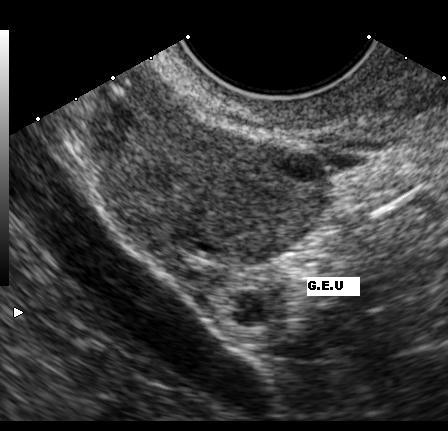

Dapat dilihat dari sebuah video, proses dalam menempatkan titik potensional dalam metode Maximum Implantation Potential atau sering disebut dengan MIP point ini dapat dilakukan dengan bantuan 3D ataupun 4D Ultrasonography. Alat USG yang biasanya digunakan untuk memeriksa perkembangan janin dalam kandungan tersebut, memiliki peran yang penting pada menentukan titik yang tepat pada metode ini.

USG tersebut berguna untuk menentukan letak yang memiliki potensi yang baik sebagai tempat calon bayi di dalam kandungan pada proses transfer eukariota diploid multisel. Biasanya dengan bantuan ultrasonography, dokter bisa membuat dua garis imajiner untuk menemukan tempat yang sesuai dengan bentuk rahim sang calon ibu tersebut. Dimana dua garis tersebut jika bertemu menjadi MIP poin dan di MIP point tersebut adalah posisi yang tepat untuk menempatkan calon bayi.

Saat dokter Anda akan memasukkan kateter ke dalam rahim melalui leher rahim, dari layar USG dapat melihat pergerakan kateter menuju MIP point. Setelah kateter tersebut mencapai MIP point, kemudian dia akan melepaskan calon bayi tersebut di bagian rongga rahim tersebut. TAnda jika calon bayi telah berada di dalam rahim, akan terlihat sebuah cahaya dari layar ultrasonography. Setelah embrio tersebut di letakkan, kateter kemudian dapat ditarik keluar.